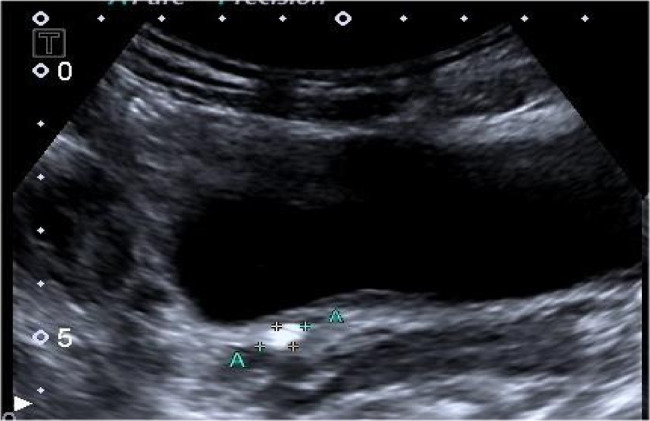

Background: To evaluate ureteral wall thickness (UWT) at the ureterovesical junction (UVJ) measured by ultrasound for predicting spontaneous passage (SP) of uncomplicated UVJ stones.

Patients and methods: We retrospectively reviewed 170 patients ≥ 18 years old, and size ≤ 10 mm of single UVJ stone, who were examined and treated in the Third People's Hospital of Yunnan Province from January 2020 to January 2024. The analysis included the size of the stones, the maximum UWT at the stone site measured by ultrasound, the degree of hydronephrosis, and the time of stone removal.According to the different results after four weeks of medical expulsive therapy (MET), the patients were separated into two categories: Stone-passing group (SPG) and non-stone-passing group (NSPG). Univariate and multivariate logistic regression analysis were utilised to evaluate the clinical predictors of MET.The receiver operating characteristic (ROC) curve was employed to evaluate the accuracy of the UWT at the UVJ in predicting successful MET.

Results: The SPG comprised 112 cases (65.9%), while the NSPG consisted of 58 cases (34.2%). Univariate analysis, employing both the chi-square test and the Mann-Whitney U test, revealed that gender, age, stone side and degree of hydronephrosis were not statistically significant. However, stone size and UWT were found to be influencing factors in regard to stone removal. Binary logistic regression analysis demonstrated that UWT and size were independent influencing factor of MET. The ROC analysis indicated that 3.705 mm was the ideal threshold for UWT, with sensitivity and specificity levels of 72.4% and 68.7%, with an area under the ROC curve (AUC) of 0.737.